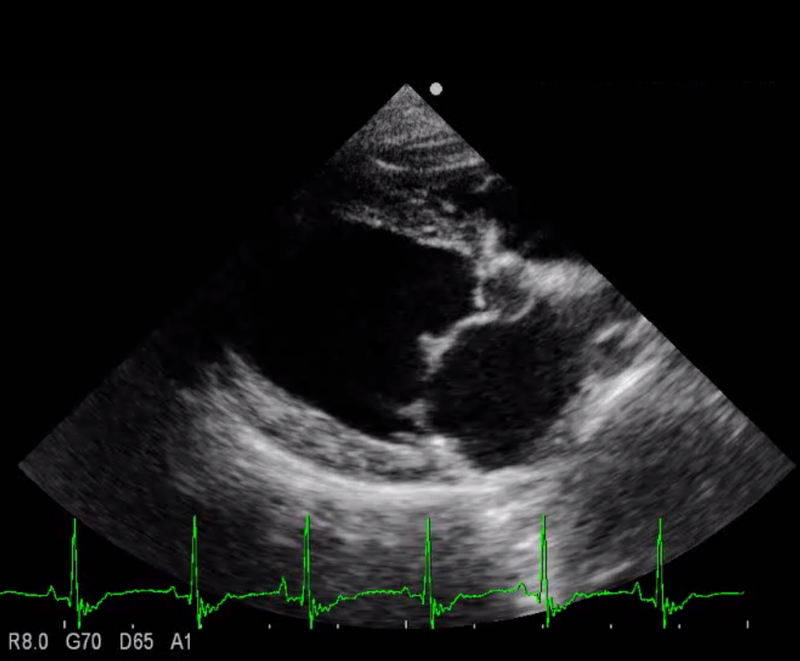

MRに罹患した犬の超音波画像所見(左心房と左心室の間に位置する僧帽弁の弁尖部に肥厚が認められる)